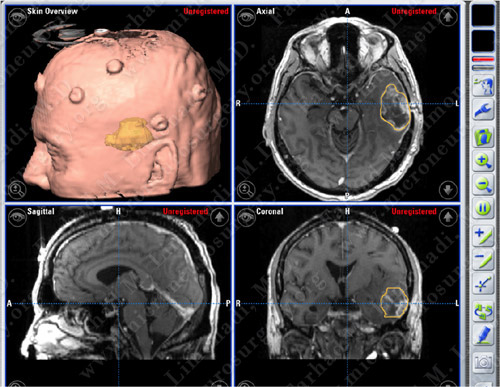

Computer Navigation

Computer navigation and stereotaxy utilized to map and localize the tumor (outlined in yellow) during surgery.